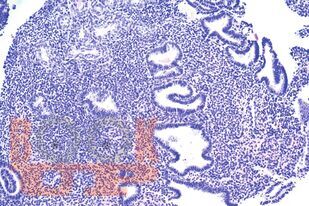

Учебное пособие содержит материалы, касающиеся терминологии, распространенности, современных классификационных принципов, морфологии и терапии эндометриальных полипов. Пособие составлено в соответствии с рабочими программами дисциплин «Патологическая анатомия», «Акушерство и гинекология» и разработано с учетом положения «Требования к структуре, содержанию и порядку оформления учебных изданий» СМК П 13-2019, утвержденного приказом ректора ФГБОУ ВО ЮУГМУ Минздрава России от 30.08.2019 № 215, введено в действие с 02.09.2019.